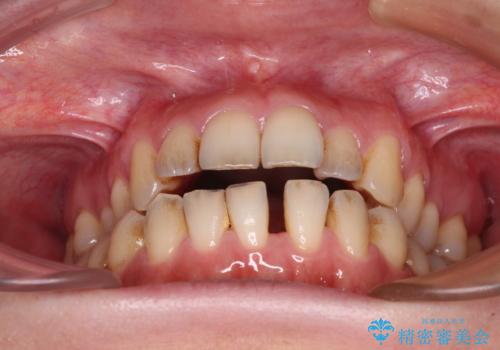

- 上下前歯の隙間を気にして来院された患者様です。

下顎前歯が1本欠損しており、上下小臼歯はクロスバイトとなり、上下前歯の接触もないという不正咬合の状態でした。

クロスバイトはワイヤー矯正が得意とするところであり、上下前歯の非接触や開咬はインビザラインの得意とするところであるので、ワイヤー装置により事前にクロスバイトを改善し、その後にインビザラインにて仕上げていくこととしました。